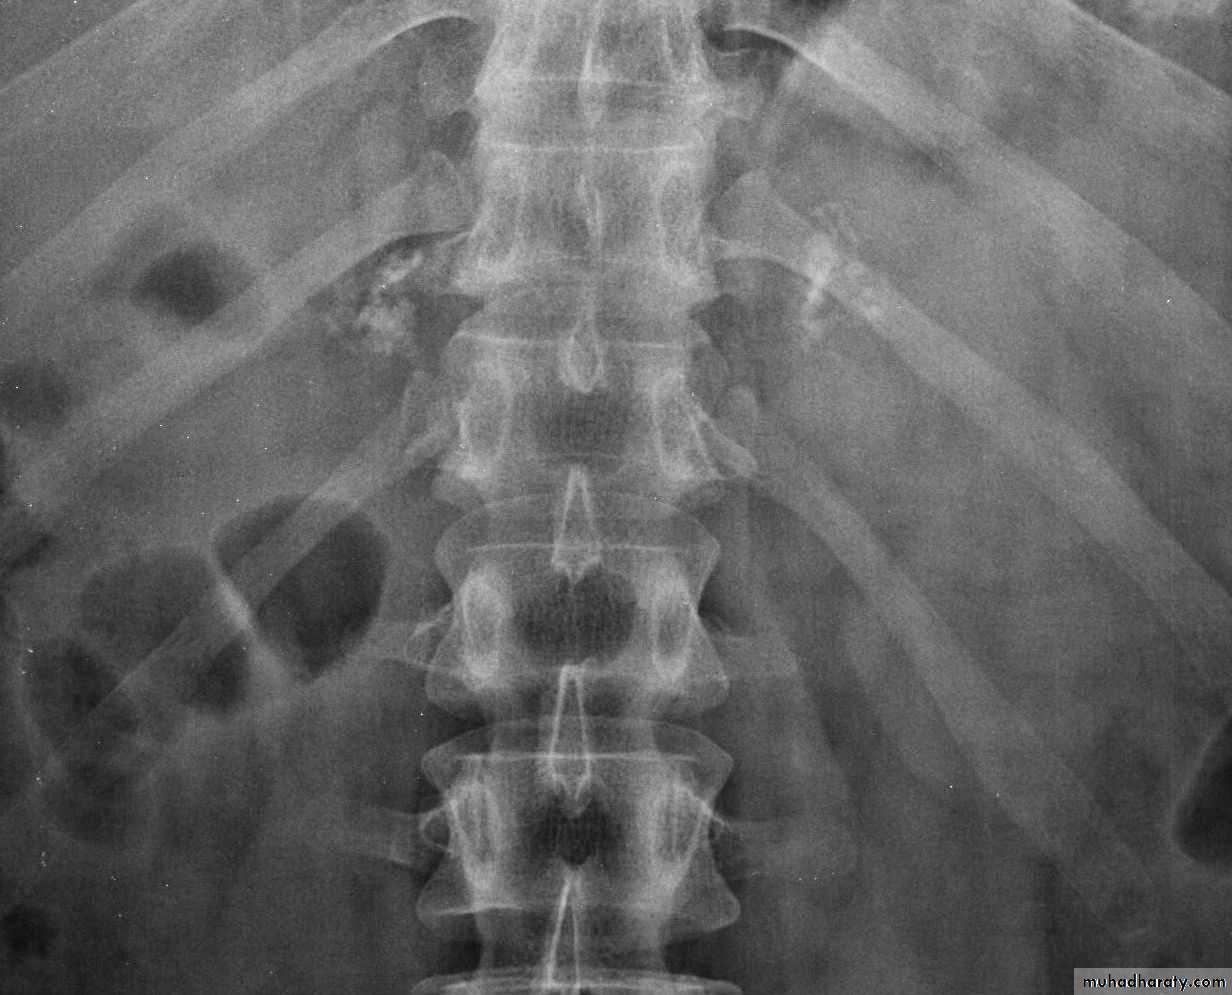

Adrenal calcification

Peritoneal cavity and retroperitoneal